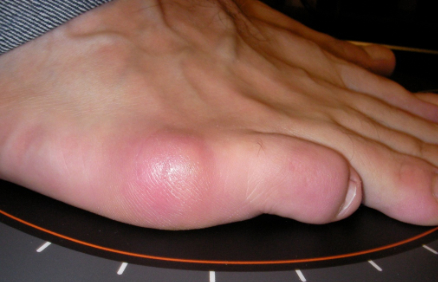

Hallux Valgus (juanete)

Hallux valgus: antes Hallux valgus: después